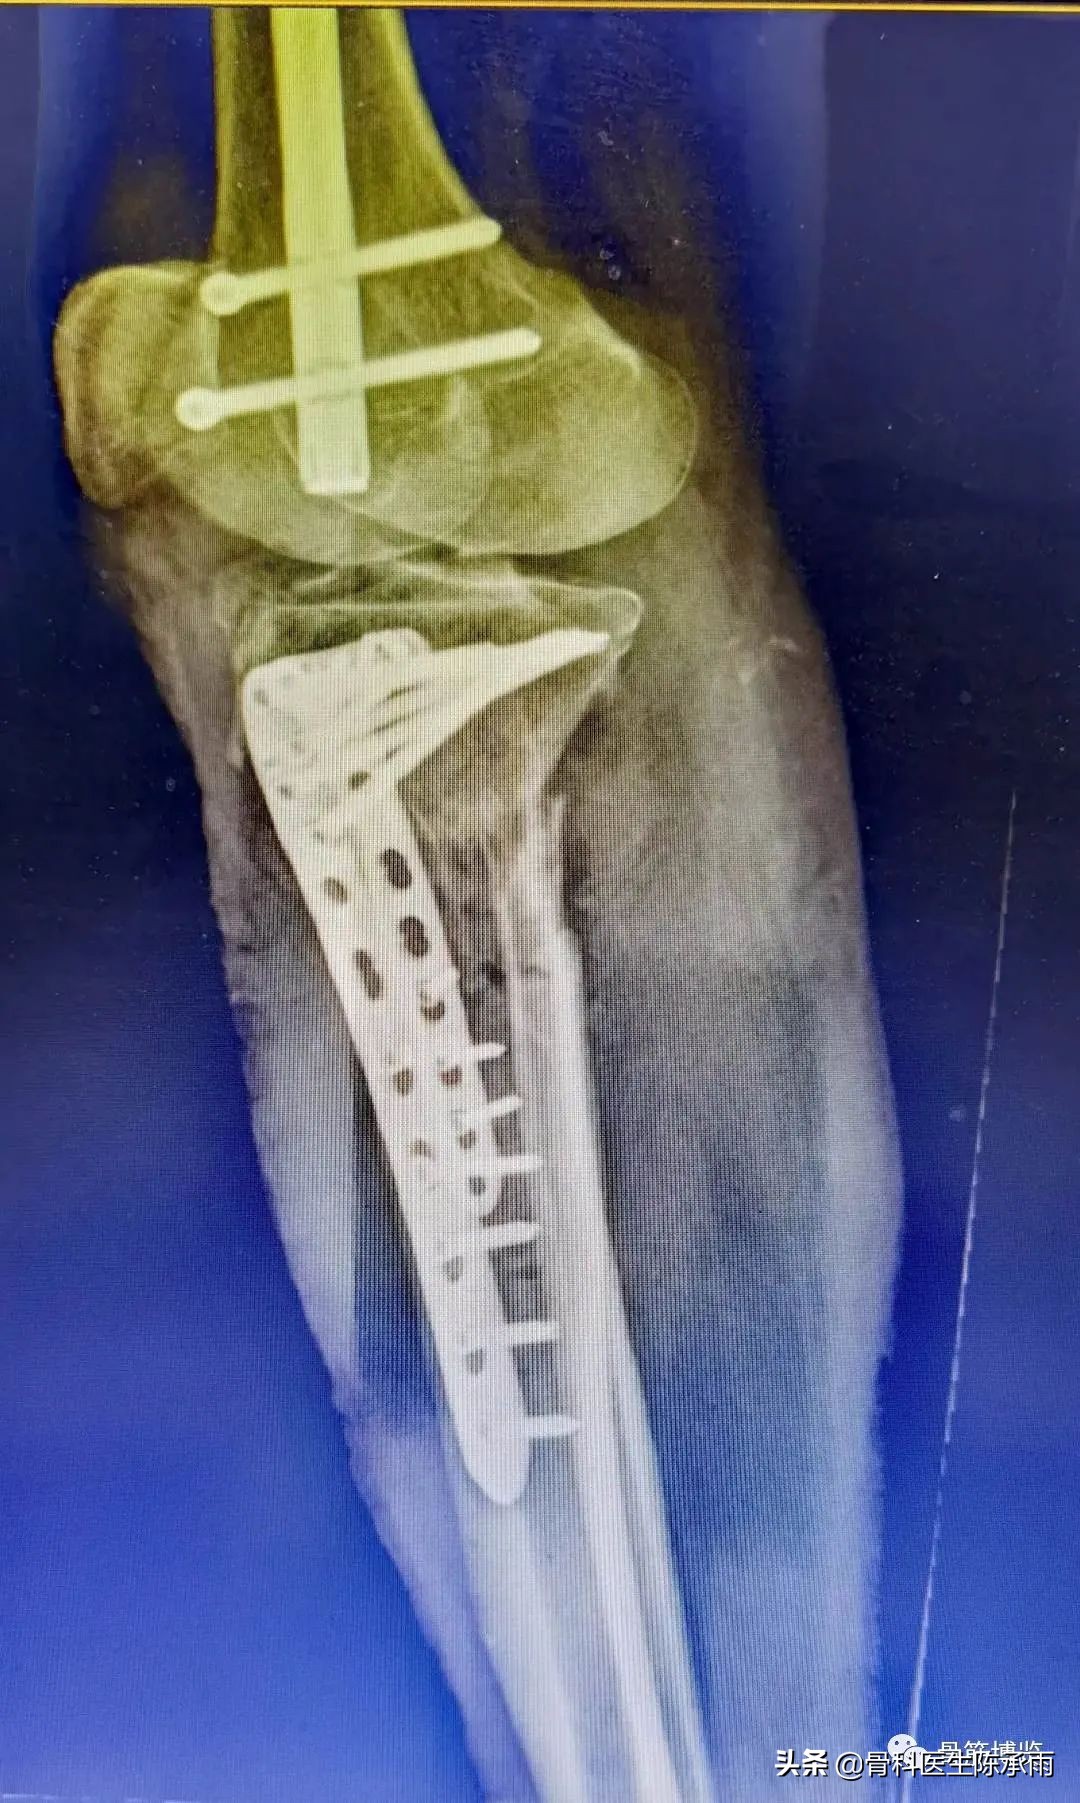

这2例患者皮肤条件差,全身多发骨折,小腿皮肤条件差,1例筋膜高压切开,1例整个小腿布满张力性水泡,胫骨骨折都在伤后30天才能手术。

下例胫平台骨折皮肤条件差,内侧板取两端小切口置入内板固定。胫骨结节处撕脱骨折以1枚拉力螺钉固定。